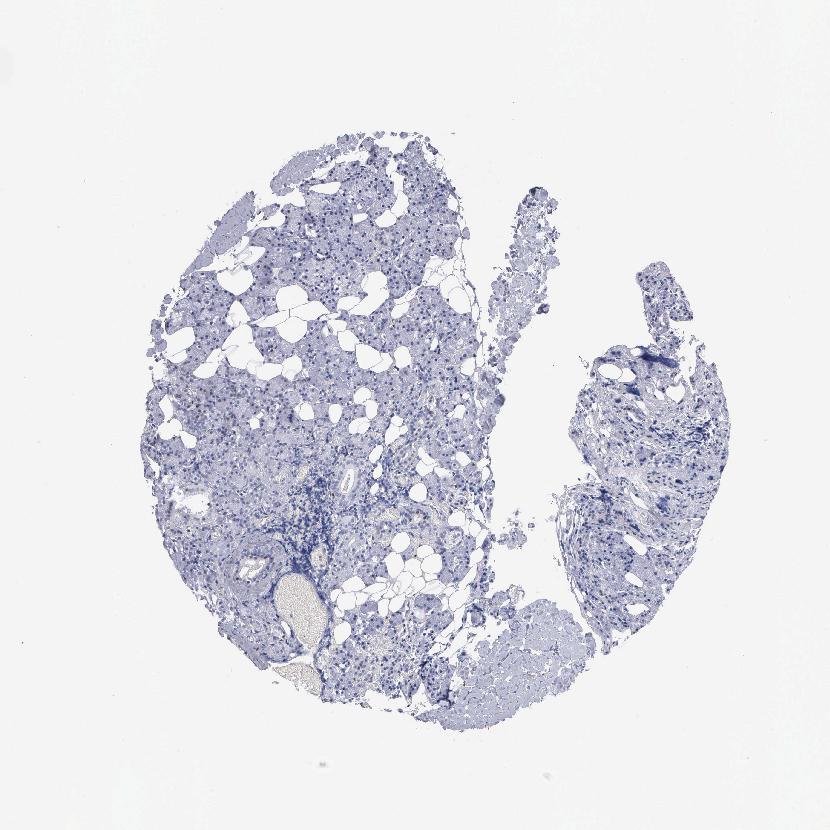

SALIVARY GLAND - Antibody stainingi

Antibody staining in the annotated cell types in the current human tissue is reported as not detected, low, medium, or high, based on conventional immunohistochemistry profiling in selected tissues. This score is based on the combination of the staining intensity and fraction of stained cells.

Each image is clickable and will lead to virtual microscopy that enables deeper exploration of all samples and also displays staining intensity scores, fraction scores and subcellular localization as well as patient and tissue information for each sample.

Antibody HPA000781

Glandular cells Not detected